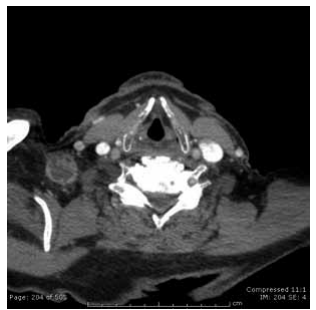

Homem de 23 anos com linfonodomegalia de 2 cm,

conforme demonstrada na imagem a seguir, com suspeita

de doença linfoproliferativa.

(Arquivo pessoal; imagem usada com autorização)

Assinale a alternativa que apresenta os cuidados cirúrgicos necessários durante a biópsia excisional.